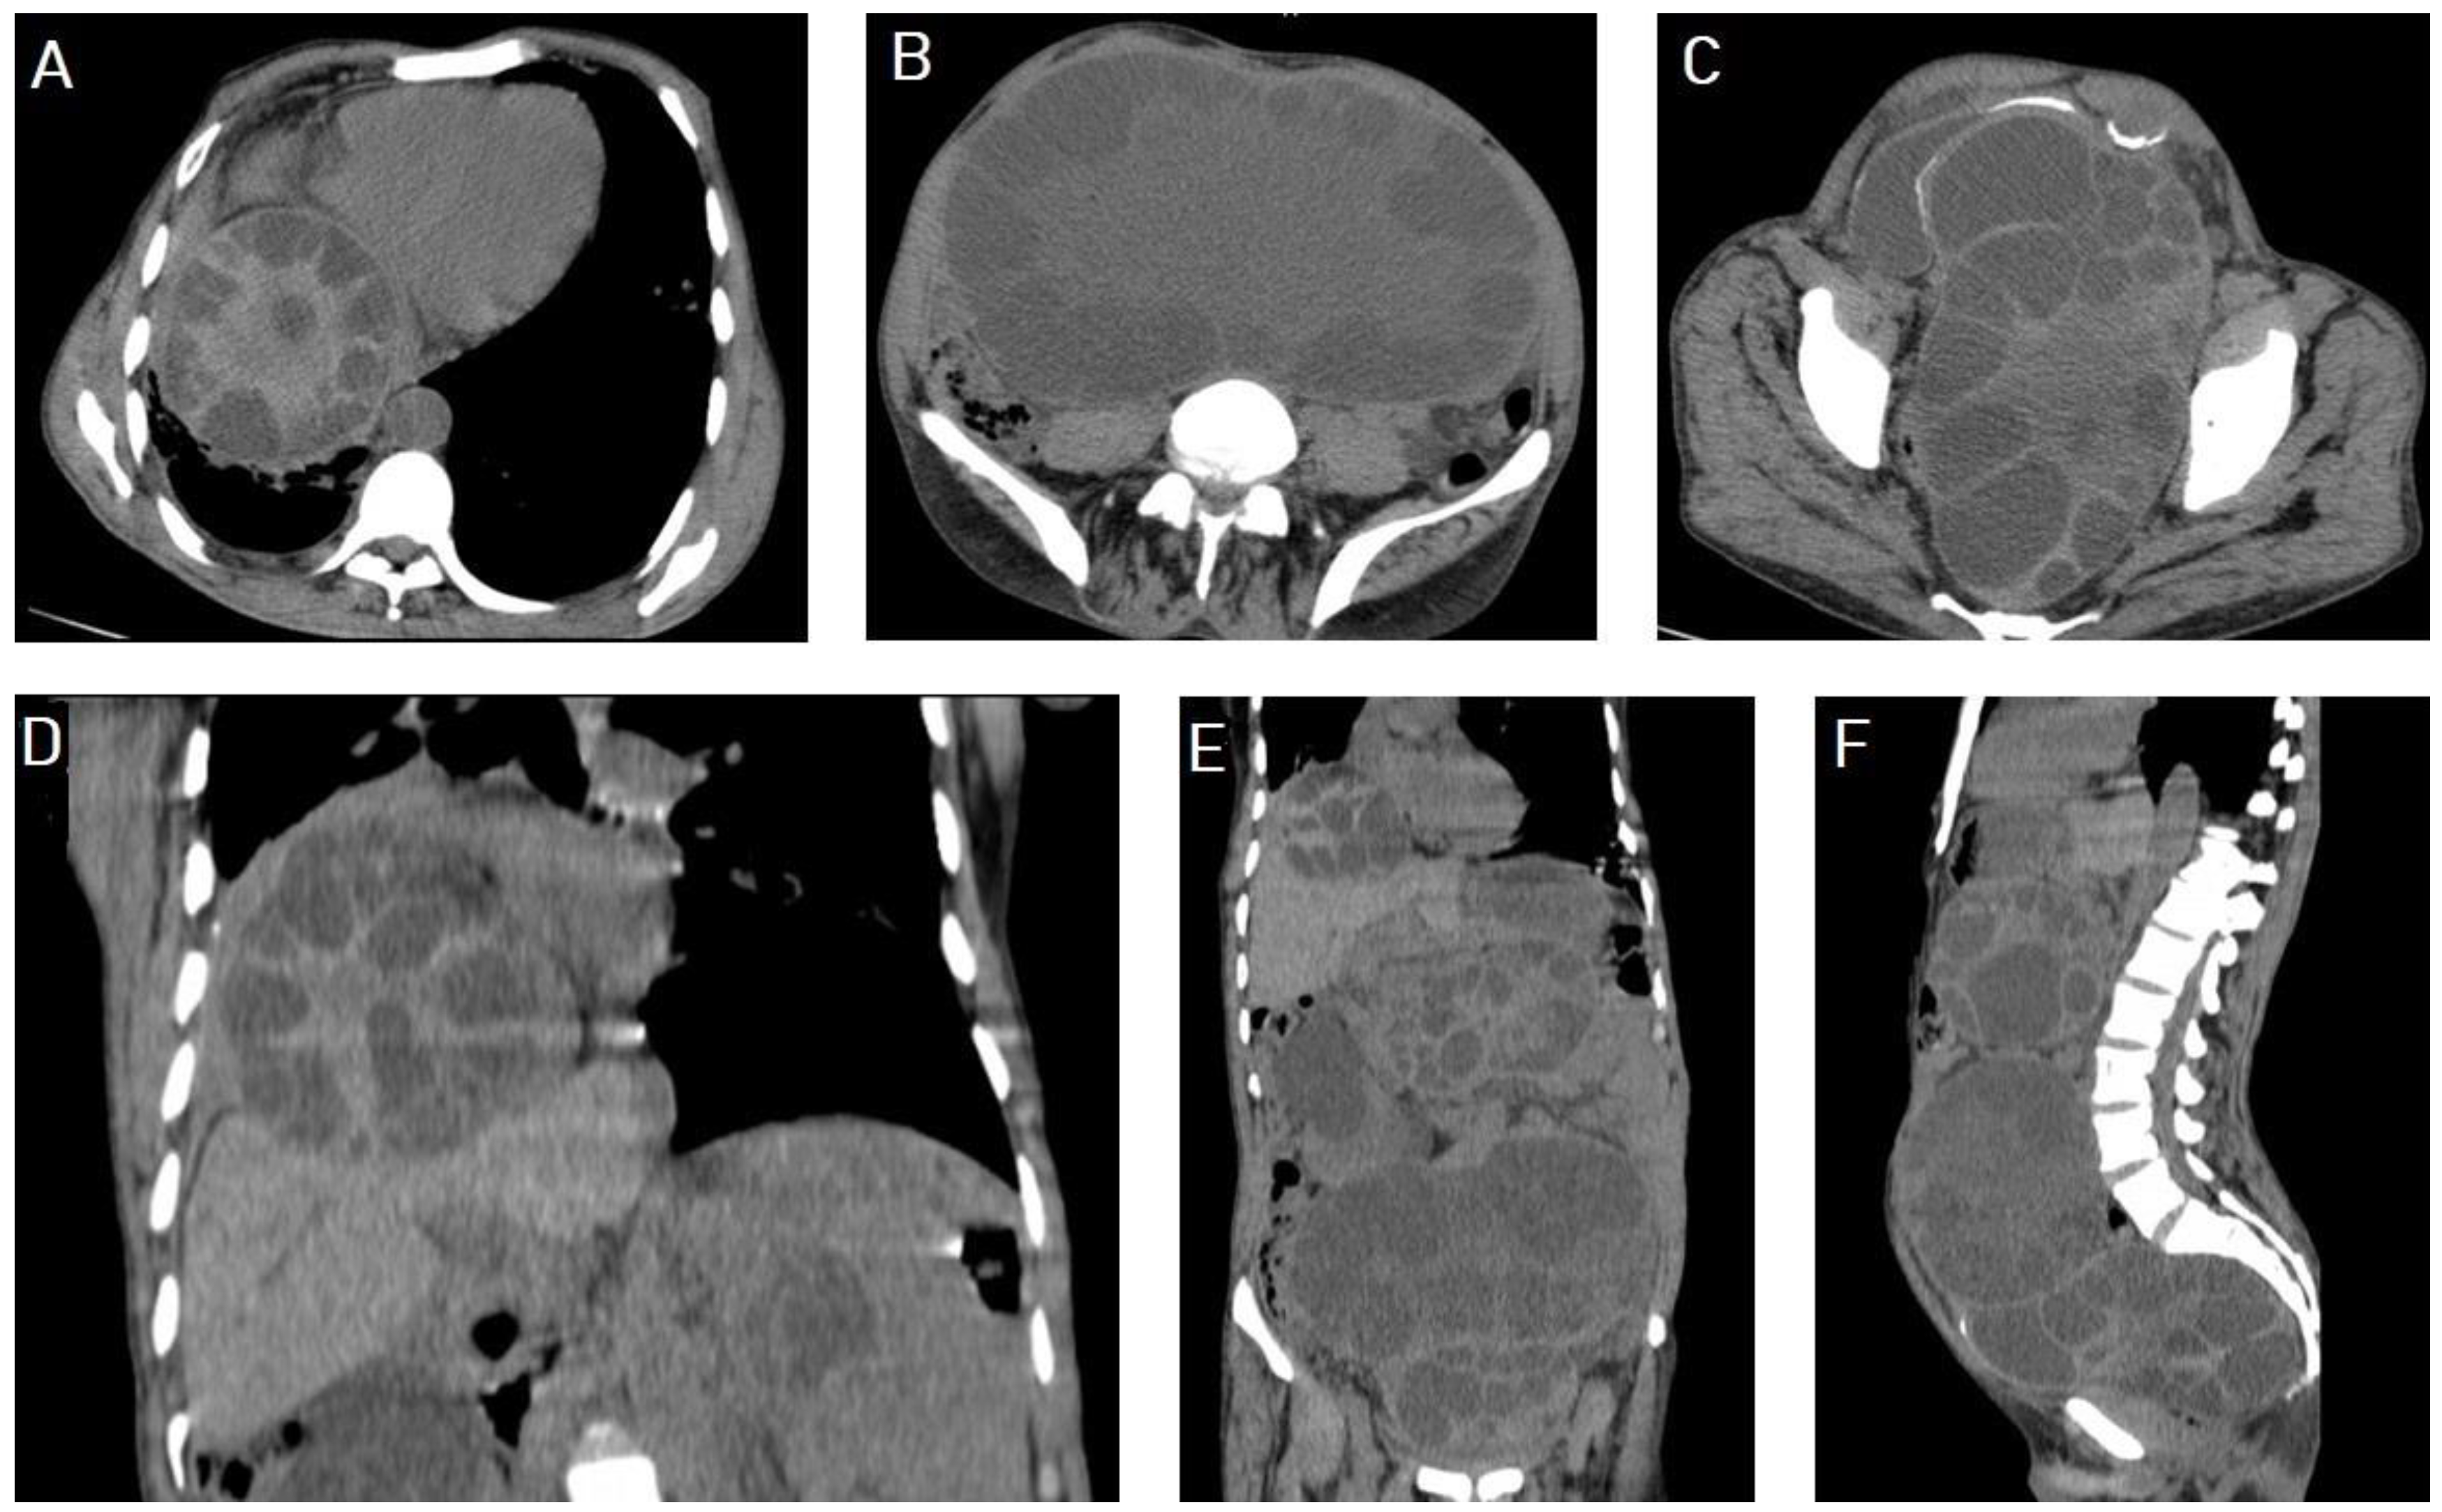

5.1. Hydatid Cysts of the Liver